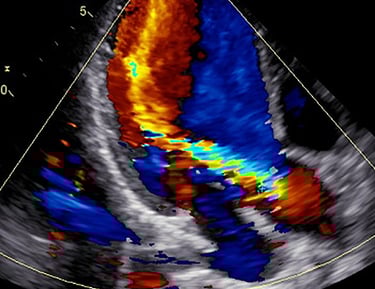

ECODOPPLER CARDÍACO COLOR

También llamado doppler cardíaco, o ecocardiograma, realizado por el dr. morisse para el diagnóstico de múltiples patologías cardiovasculares, evaluación deportiva, estudio de soplos y demás indicaciones de diversa índole cardiovascular. gran utilidad clínica